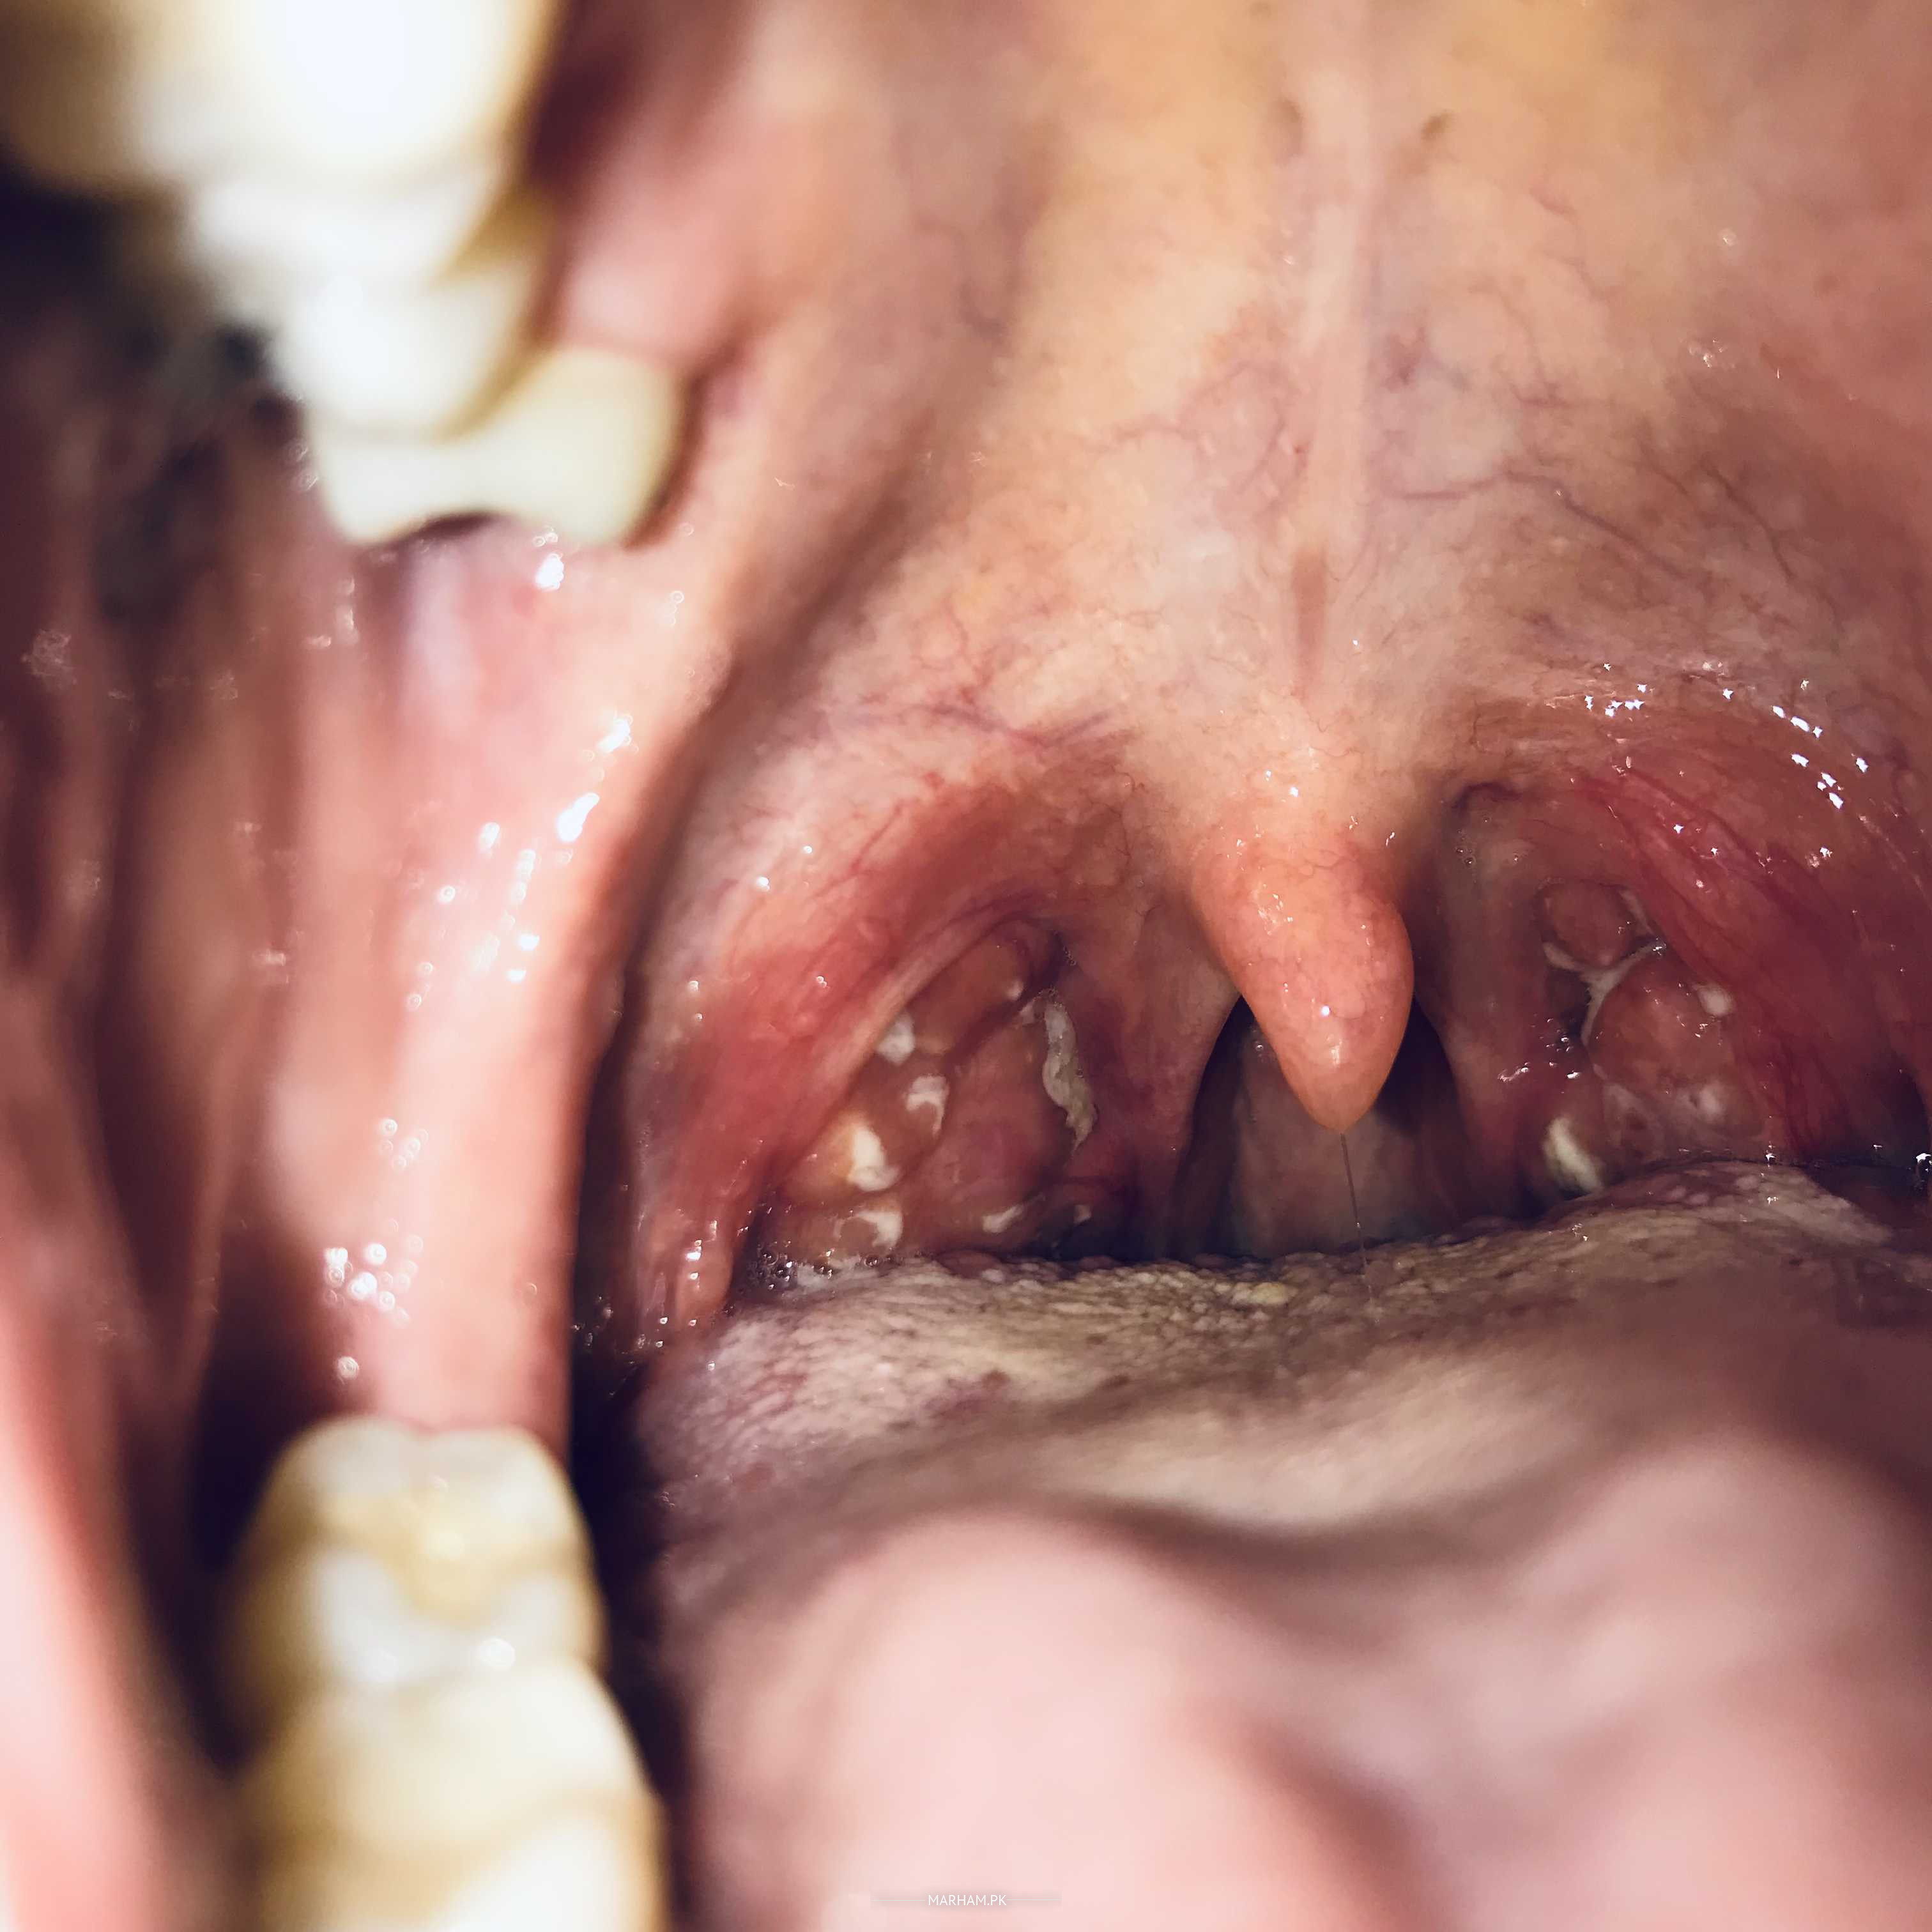

I hav tonsils stones since yesterday. Thy are painful and cause bad breath.

These are not stones. This is acute follicular infection of tonsils You need proper Antibiotics injections Get consultation from ENT specialist

ye medicine se desolve ho skty hain or without surgery ap bilkul theek ho jain gi Jo cheezain ap ko problem kr rahi hain wo chony ki zaroorat nai hy ap Zaroor lain ap ko koi problem nai ho gi ap detail bat kr lain